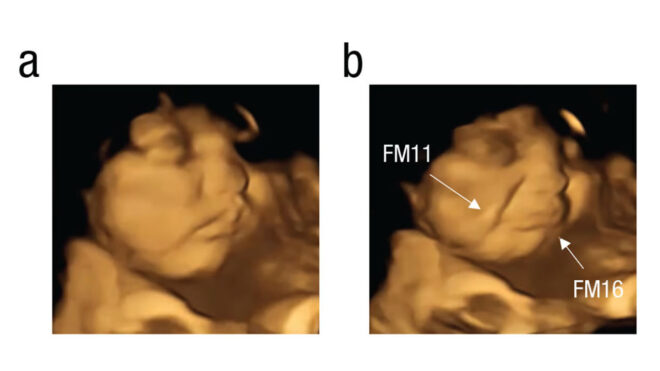

Yeni araştırma ile bu süreci yukarıda da görebileceğiniz üzere görselleştiren ve ilk kez direkt kanıt elde eden araştırma ekibi, burada uzun zamandır kullanımda olan 4D ultrason teknolojisinden yardım alıyor. 4D ultrason ile anne karnından üç boyutlu görüntü alabilen ekip, bir anne “havuç” tükettiği zaman bebeğinin gülümsediğini, “kıvırcık lahana” tükettiği zaman ise ağlıyormuş gibi bir surata geçiş yaptığını karşımıza getiriyor.

Görüntüleri anne gıdayı tükettikten 20 dakika sonra yakalayan ve gıda öncesi bir kontrol taraması da kaydeden araştırmacılar, süreçte 100 farklı hamile kadın üzerinde testler gerçekleştirmiş ve büyük oranda benzer bir sonuç elde etmiş.